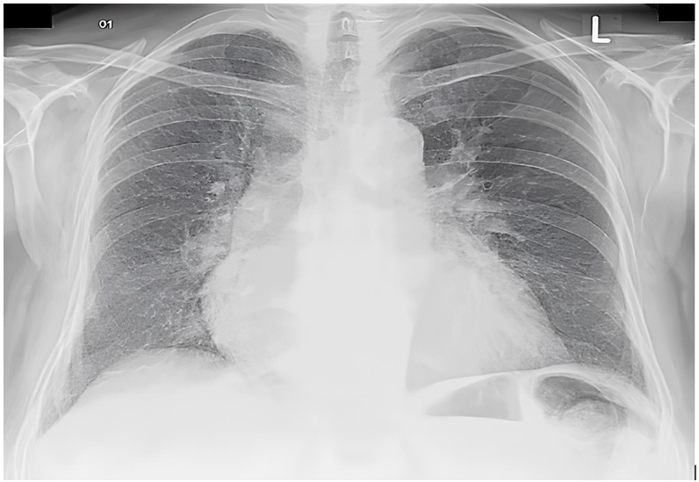

Inicialmente, o paciente é colocado em máscara de Hudson a 10 L/min com infusão de nitroglicerina endovenosa, apresentando melhora dos sintomas. Na sequência, o paciente apresenta PA 76/40 mmHg e FC de 120 bpm. Além de suspender a nitroglicerina, qual é a próxima conduta mais adequada para esse paciente?